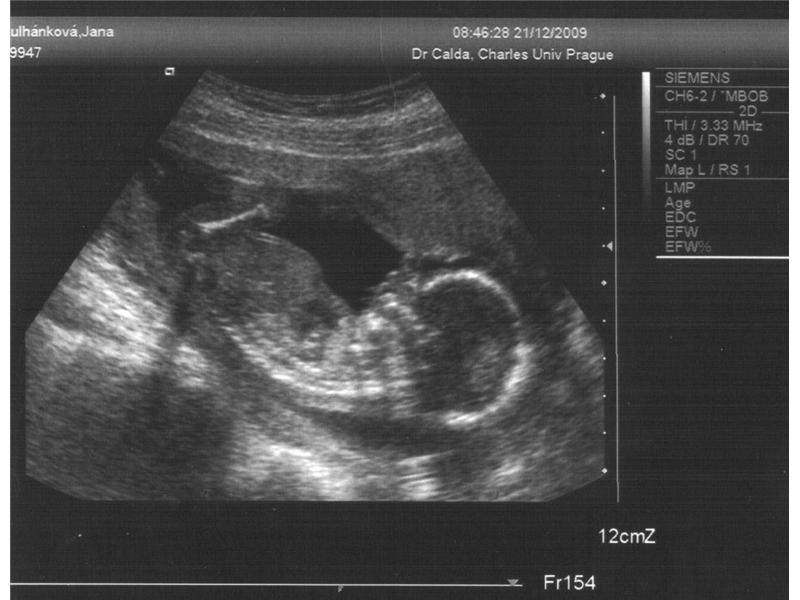

2. trimestr